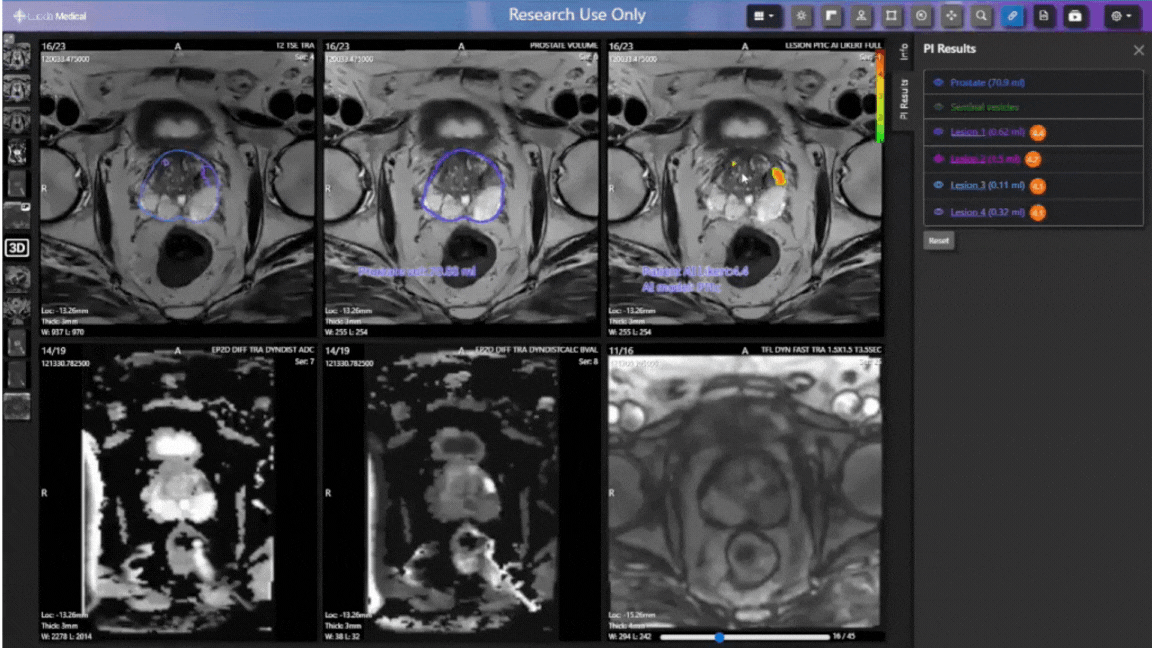

Pi™, Prostate Intelligence™ es un sistema de machine learning, diseñado como soporte de los especialistas de imagen para localizar la presencia de lesiones y la detección del cáncer de próstata. Sus análisis se muestran en un informe y en el PACS desde el fueron enviadas las imágenes de resonancia magnética.

Segmentaciones de alta calidad: la generación de segmentaciones automáticas, comparables a las anotaciones de expertos humanos, facilita la visualización, el análisis y la selección de biopsias en el proceso de detección del cáncer de próstata.